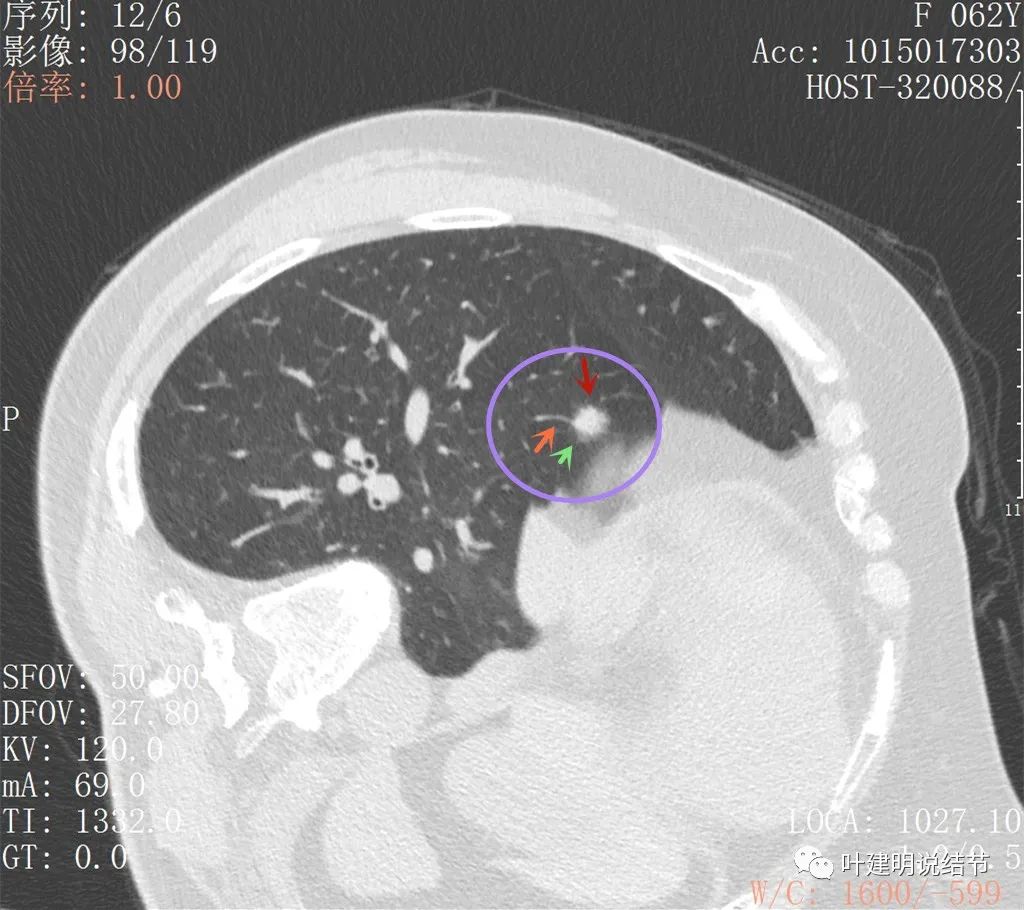

上图见病灶较为典型的恶性征象,边缘有细毛刺,也有少许磨玻璃(绿色所指),还有血管进入(桔色),总体上看,像颗杨梅